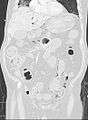

Pneumatosis intestinalis (also called intestinal pneumatosis, pneumatosis cystoides intestinalis, or pneumatosis coli) is pneumatosis of an intestine, that is, gas cysts in the bowel wall.[1] As a radiological sign it is highly suggestive for necrotizing enterocolitis. This is in contrast to gas in the intestinal lumen (which is relieved by flatulence). In newborns, pneumatosis intestinalis is considered diagnostic for necrotizing enterocolitis, and the air is produced by bacteria in the bowel wall.[2] The pathogenesis of pneumatosis intestinalis is poorly understood and is likely multifactorial. PI itself is not a disease, but rather a clinical sign. In some cases, PI is an incidental finding, whereas in others, it portends a life-threatening intra-abdominal condition.